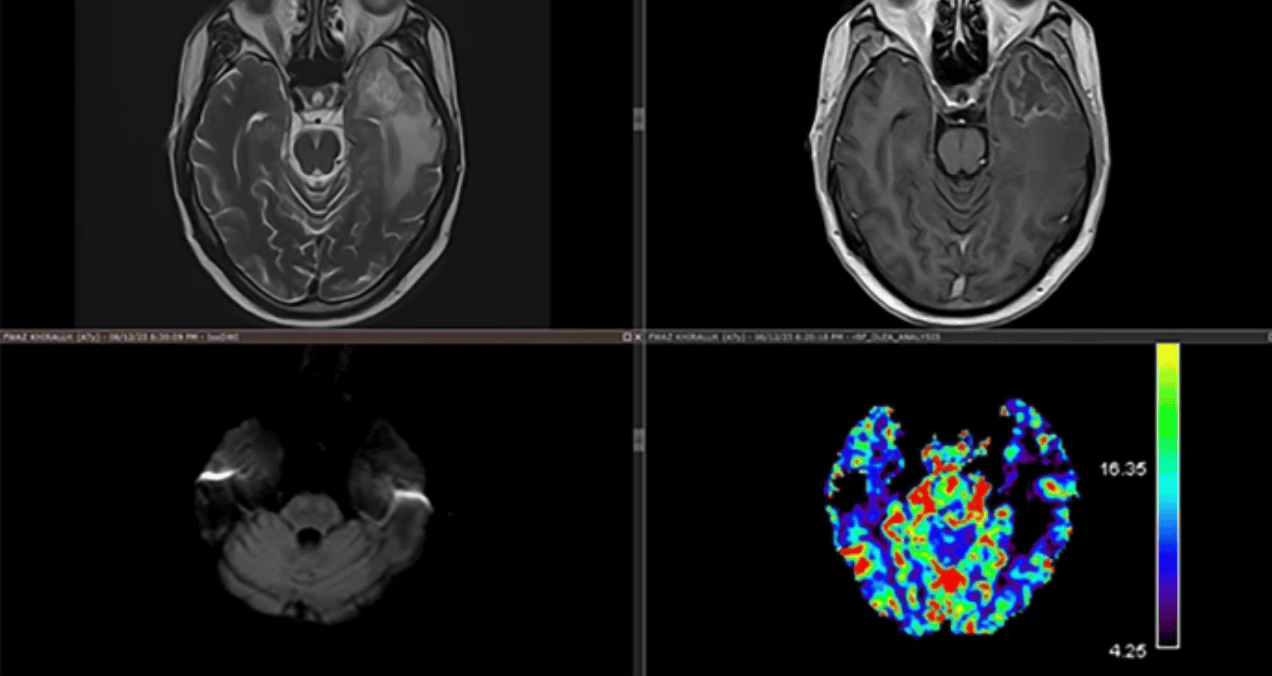

Una imagen del espectro de efectos a corto plazo de la prensa que muestra un pico alto de lactato con colina normal, excluyendo alta celularidad o destrucción celular como se ve en lesiones neoplásicas y sugiriendo necrosis debido a hipoxia (niveles altos de lactato en la espectroscopia de resonancia magnética)

La resonancia magnética cerebral con secuencias avanzadas mostró una lesión en lóbulo temporal izquierdo de 18x13 mm con características típicas de necrosis por radiación: hiperseñal en T2/FLAIR, realce anular en T1 con gadolinio, restricción en difusión y espectroscopia con elevación de lactato (2.3 ppm) y reducción de NAA (1.8 ppm). El estudio de perfusión no mostró hipervascularización, descartando recidiva tumoral. El EEG demostró actividad delta focal temporal izquierda sin descargas epileptiformes.